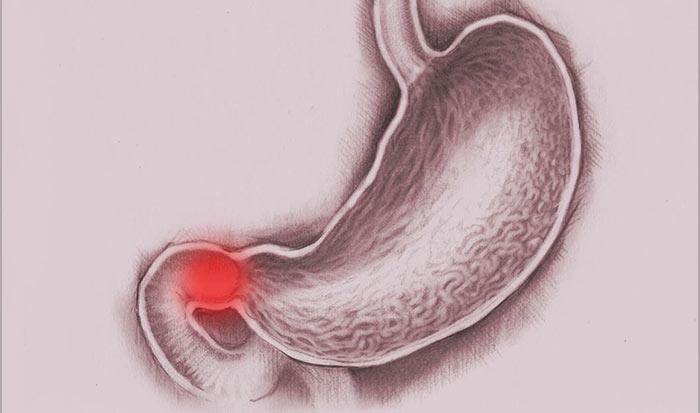

Информация и фотографии о хроническом гастрите и дуодените